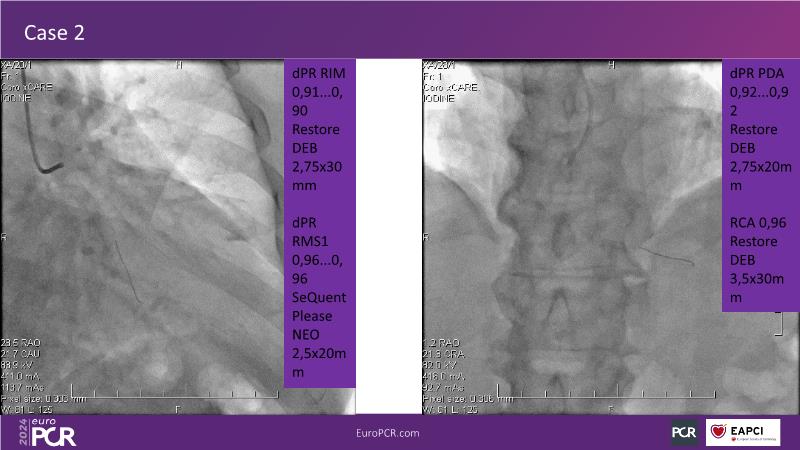

Physiology guided post-DCB treatment to safely limit stenting. Validation in complex clinical settings with the optical Optowire III pressure guidewire

Follow this session to discover how accurate resting index can inform decision-making for DCB in CTO patients and understand the role of physiology in a new PCI workflow for complex MVD. Thus, you will learn about a DCB intention-to-treat strategy guided by post-PCI coronary physiology in complex lesions, review new procedural techniques and workflows from real-world cases, and explore the pros and cons of this novel approach.

- To learn about DCB intention-to-treat strategy guided by post-PCI coronary physiology in complex lesions